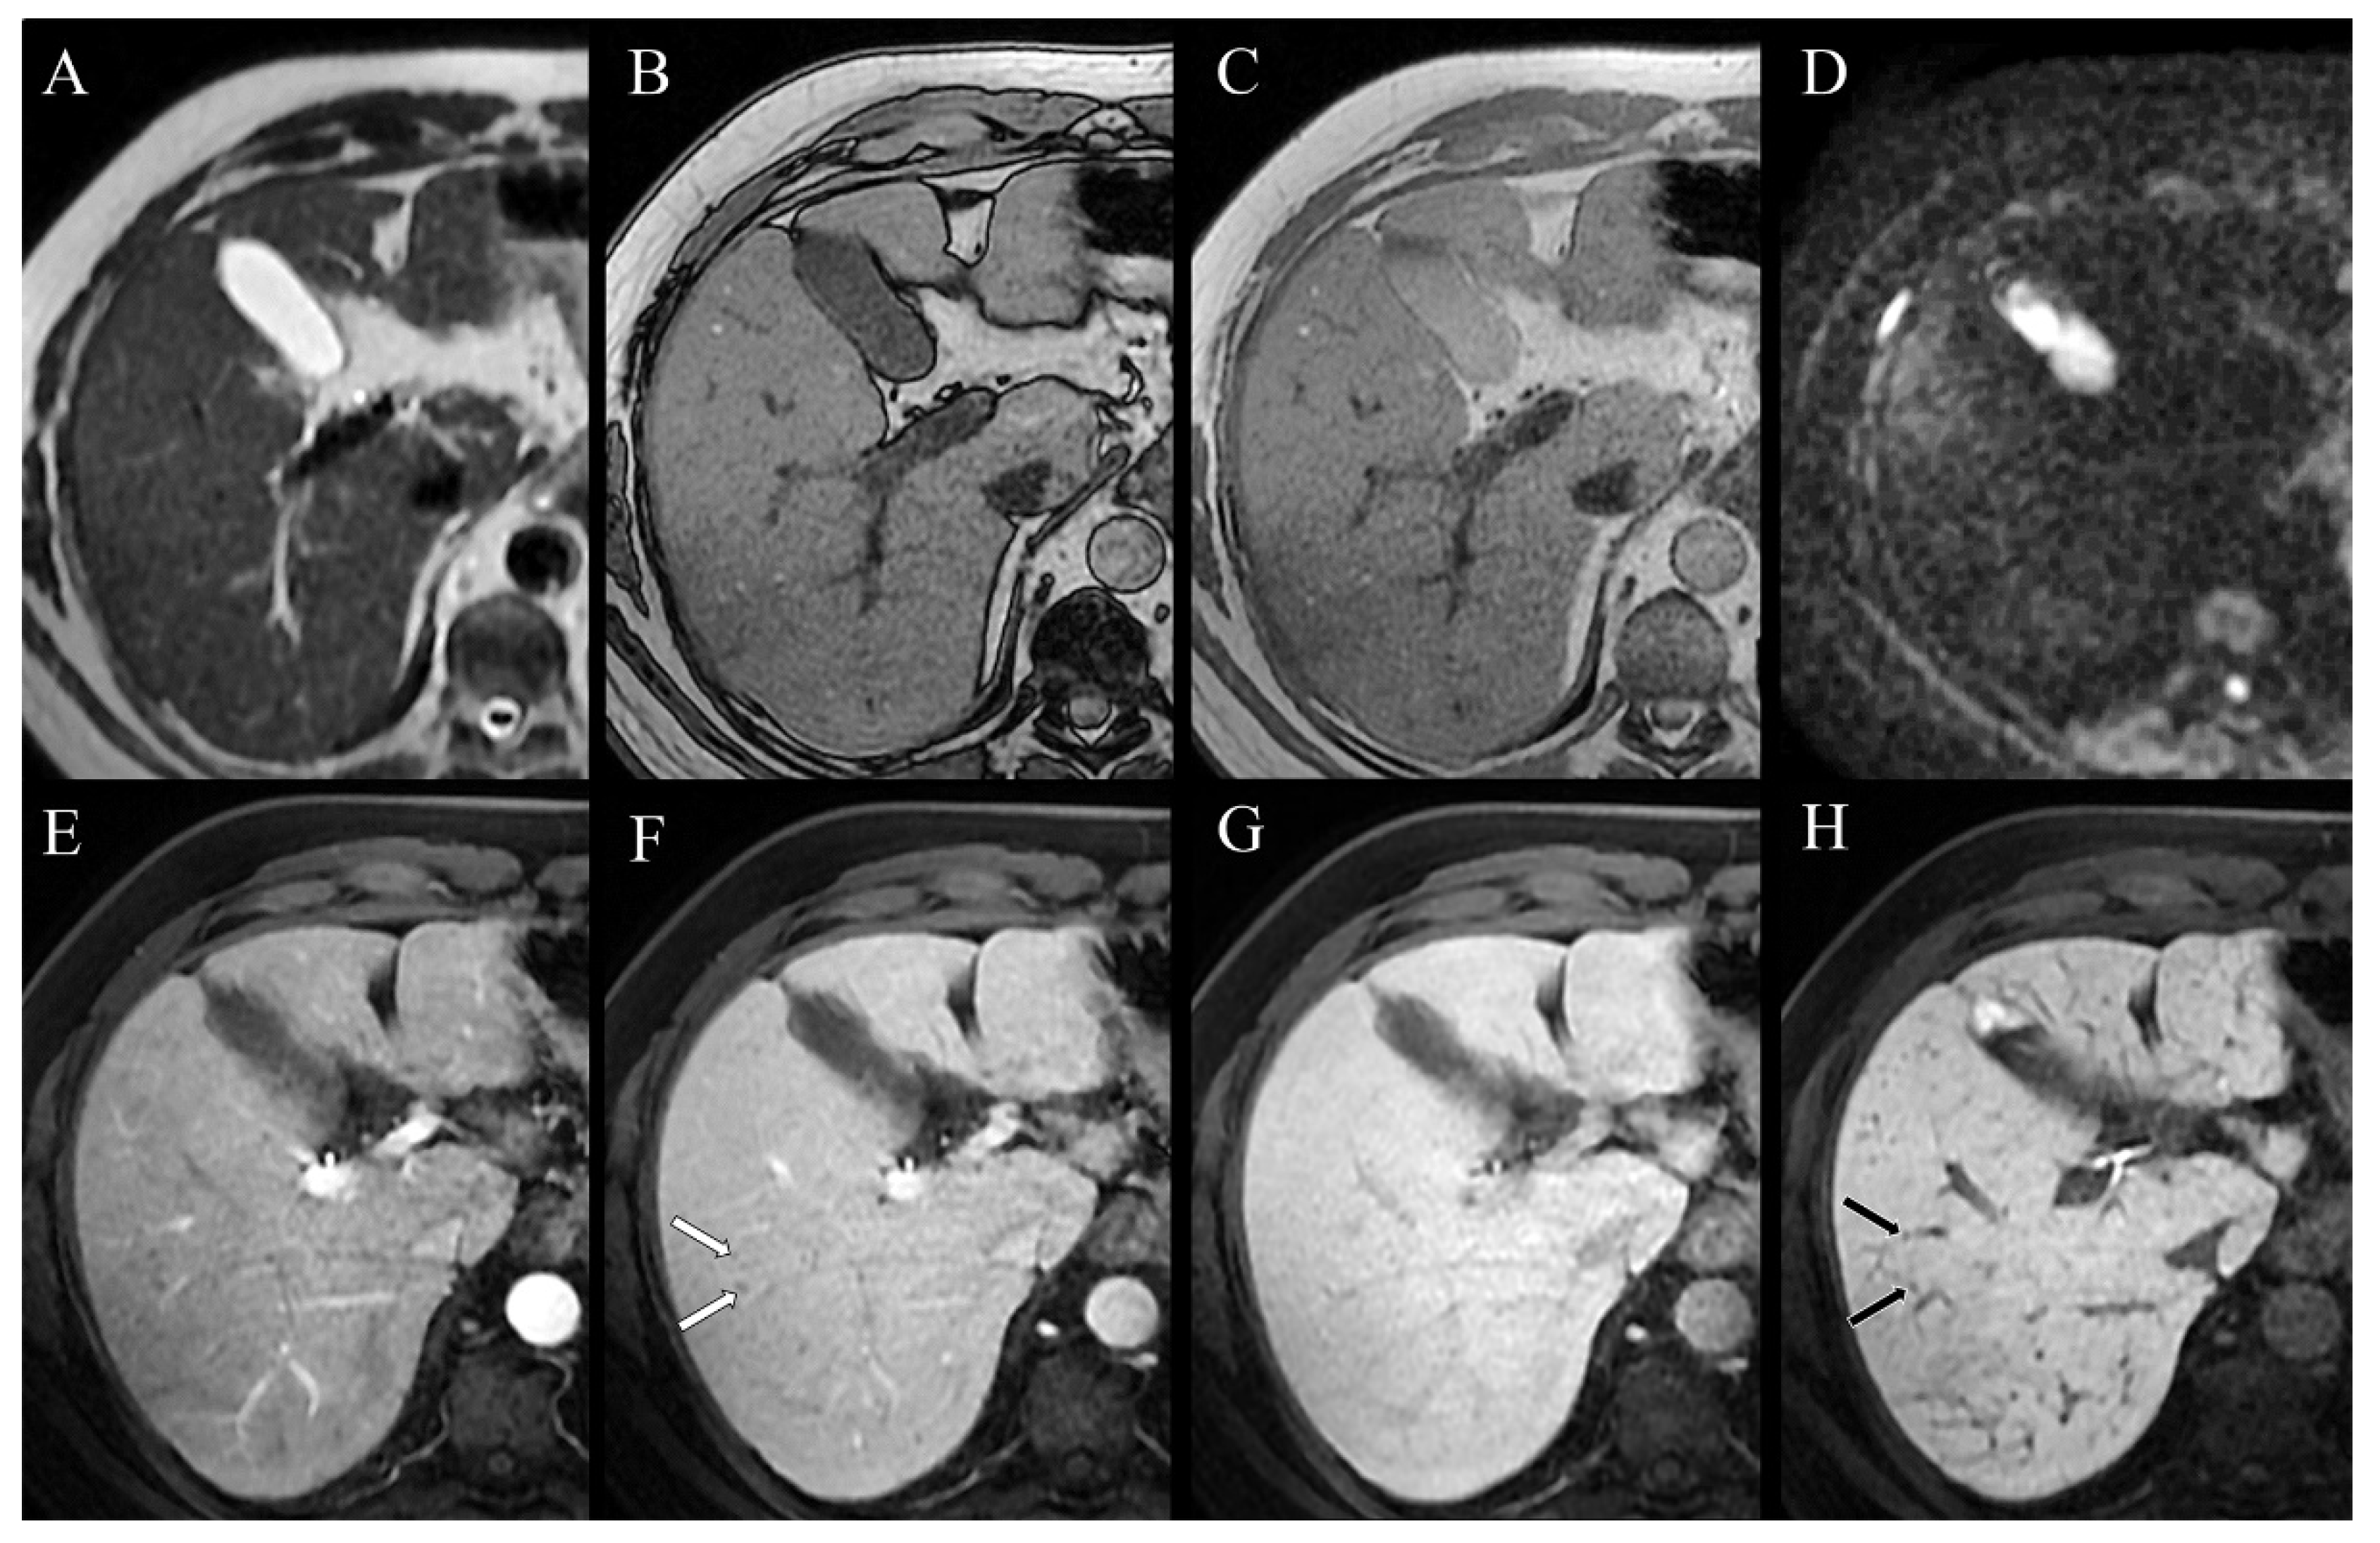

The differential diagnosis included tuberculosis, sarcoidosis, and lymphoma. The QuantiFERON-TB test was negative, excluding the hypothesis of tuberculosis in a patient with no history or signs of this disease. Laboratory tests demonstrated elevated levels of angiotensin-converting enzyme (135 U/L, with normal values of 13–64 U/L) and neuron-specific enolase (16.6 µg/L, with normal values < 12.5 µg/L), whereas alpha-fetoprotein (AFP), carcinoembryonic antigen (CEA), carbohydrate antigen (CA19-9), and viral hepatitis serology were negative, as well as the complete blood count. Furthermore, an elevation of ALP level was detected (240 U/L, normal values of 30–120 U/L), supporting the hypothesis of biliary involvement due to the lesions demonstrated by CT. Subsequently, the patient underwent 18F-FDG-PET/CT, which showed increased 18F-FDG uptake in all of the parenchymal lesions and lymph nodes revealed by CT, including the diffuse hepatobiliary lesions. Focal uptakes were also detected in districts where the CT scan did not reveal evident lesions, such as the laterocervical lymph nodes, heart (subsequently confirmed by cardiac MRI), lumbar spine, left femur bone marrow, and in a subdiaphragmatic area in the liver. Color Doppler sonography and transient elastography (TE, FibroScan ®, Echosens, Paris, France) revealed liver fibrosis and slow portal flow. Hence, the need to confirm the hypothesis of sarcoidosis, excluding with certainty the possibility of lymphoma, coupled with the need to confirm the nature of hepatobiliary lesions and possible indirect signs of portal hypertension required to ascertain the hepatic venous pressure gradient and perform transjugular liver biopsy. The first examination excluded portal hypertension, and the histological evaluation confirmed the hepatobiliary sarcoid involvement by demonstrating non-necrotizing granulomas. Therefore, all of the lesions highlighted by imaging were attributed to the final diagnosis of sarcoidosis. The patient was then treated with prednisone, with significant improvement in pulmonary symptoms and normalization of ALP level. Since this normalization does not necessarily correlate with regression of hepatobiliary sarcoidosis, MRI was chosen as the follow-up imaging modality of the hepatobiliary lesions. MRI, MRCP, and functional MRCP after infusion of Gd-EOB-DTPA (Primovist®, Bayer HealthCare Pharmaceuticals, Berlin, Germany) confirmed innumerable lesions in the spleen and the liver, but dimensionally and numerically reduced if compared to the previous CT scan. This feature ensured that the decrease in ALP levels was linked to the reduction in sarcoidotic hepatobiliary involvement. Sarcoidotic granulomas, widespread in the liver, showed a low signal on T1-weighted and T2-weighted images, no restriction on diffusion-weighted images (DWIs), and appeared hypointense before and after infusion of contrast medium (Figure 4A–H).

Figure 4.

Abdomen magnetic resonance: (A) T2w, (B) T1w out-of-phase, (C) T1w in-phase, (D) DWI, (E) arterial phase, (F) portal venous phase, (G) delayed phase, and (H) hepatobiliary phase images. Millimeter-sized lesions spread throughout the whole liver appear hypointense in all sequences, and do not show enhancement after administration of contrast medium.

Furthermore, in our study, an MRI of the liver was performed as a follow-up after prednisone therapy. To the best of our knowledge, there is only one other case in the English literature [22] in which an MRI of the liver was performed as a post-therapy follow-up in hepatic sarcoidosis. The differences between our experience and that of Jung et al. are that the latter used superparamagnetic iron oxide as the contrast medium instead of Gd-EOB-DTPA, which we used in our study, and that they did not perform MRCP. In our case, liver lesions showed a low signal in both T2-weighted and T1-weighted sequences, with no signal drop between in- and out-of-phase, and no diffusion restriction on DWIs. Furthermore, after the administration of the Gd-EOB-DTPA contrast medium, no lesion enhancement was appreciable in any phase of the study. In the literature, hepatobiliary sarcoidotic lesions are reported to be slightly hypo-isointense on T1-weighted images, present a low signal on T2-weighted sequences, and not show notable enhancement after contrast medium administration [26]. However, a hyperintense T2 signal has also been reported in the event of active inflammation [22,27], size increase, and coalescence of a 6 cm granuloma [22]. Being aware of this signal pattern may be helpful in differentiating sarcoid lesions from hepatic cancer nodules or metastases, the latter tending to demonstrate higher signal intensity on T2-weighted fat-saturated sequences [28]. Moreover, in the case of diffuse hepatobiliary involvement in sarcoidosis, a reported finding of biliary involvement is the evidence of high T2 signal intensity in periportal areas [26,29], due to the tendency of granulomas to concentrate in the periportal space, thickening it [30], and leading to focal narrowing of the biliary tract. Our case is consistent with previous reports concerning radiological findings. In particular, our patient’s lesions’ low signal on T2-weighted sequences and DWIs was attributable to the good response to prednisone therapy, which reduced both inflammation activity and granuloma size.